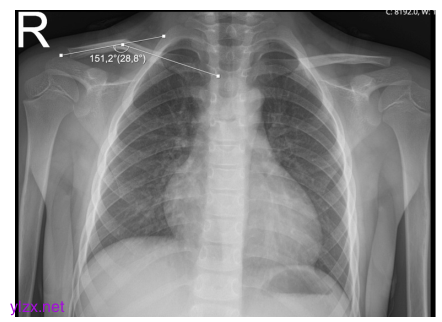

锁骨角度测量示例。通过测量穿过骨折锁骨髓质中点的线之间的角度来确定角度。